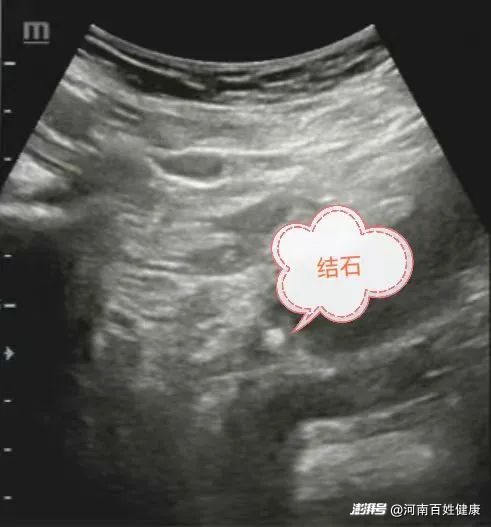

彩超提示

結(jié)石大小約0.6X0.7cm

需體外碎石